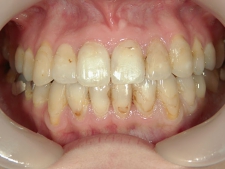

矯正歯科 治療後矯正歯科 全顎ワイヤー矯正 治療後矯正歯科(全顎ワイヤー矯正)治療後

矯正歯科 治療後

no.7_6967_治療後_右_01_640_480_やや高画質.jpgno.7_6967_治療後_正面_01.jpgno.7_6967_治療後_左_01.jpg